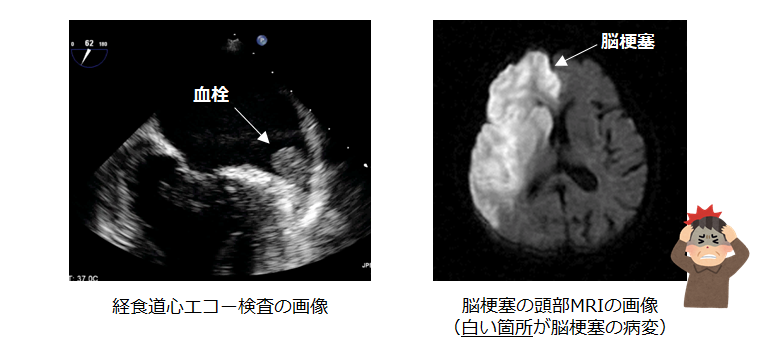

心臓の中における血流が滞ることによって血栓(血のかたまり)が形成されます。

それが全身に飛ぶことによって様々な塞栓症を引き起こします。特に重大なのが脳梗塞で、もともと血圧が高い方や糖尿病をお持ちの方、75歳以上の方が発症しやすいと言われています(※)。また心房細動が原因で発症する脳梗塞は他の原因よりも重症化することが 知られています。(下記はいずれも当院実施の検査画像)